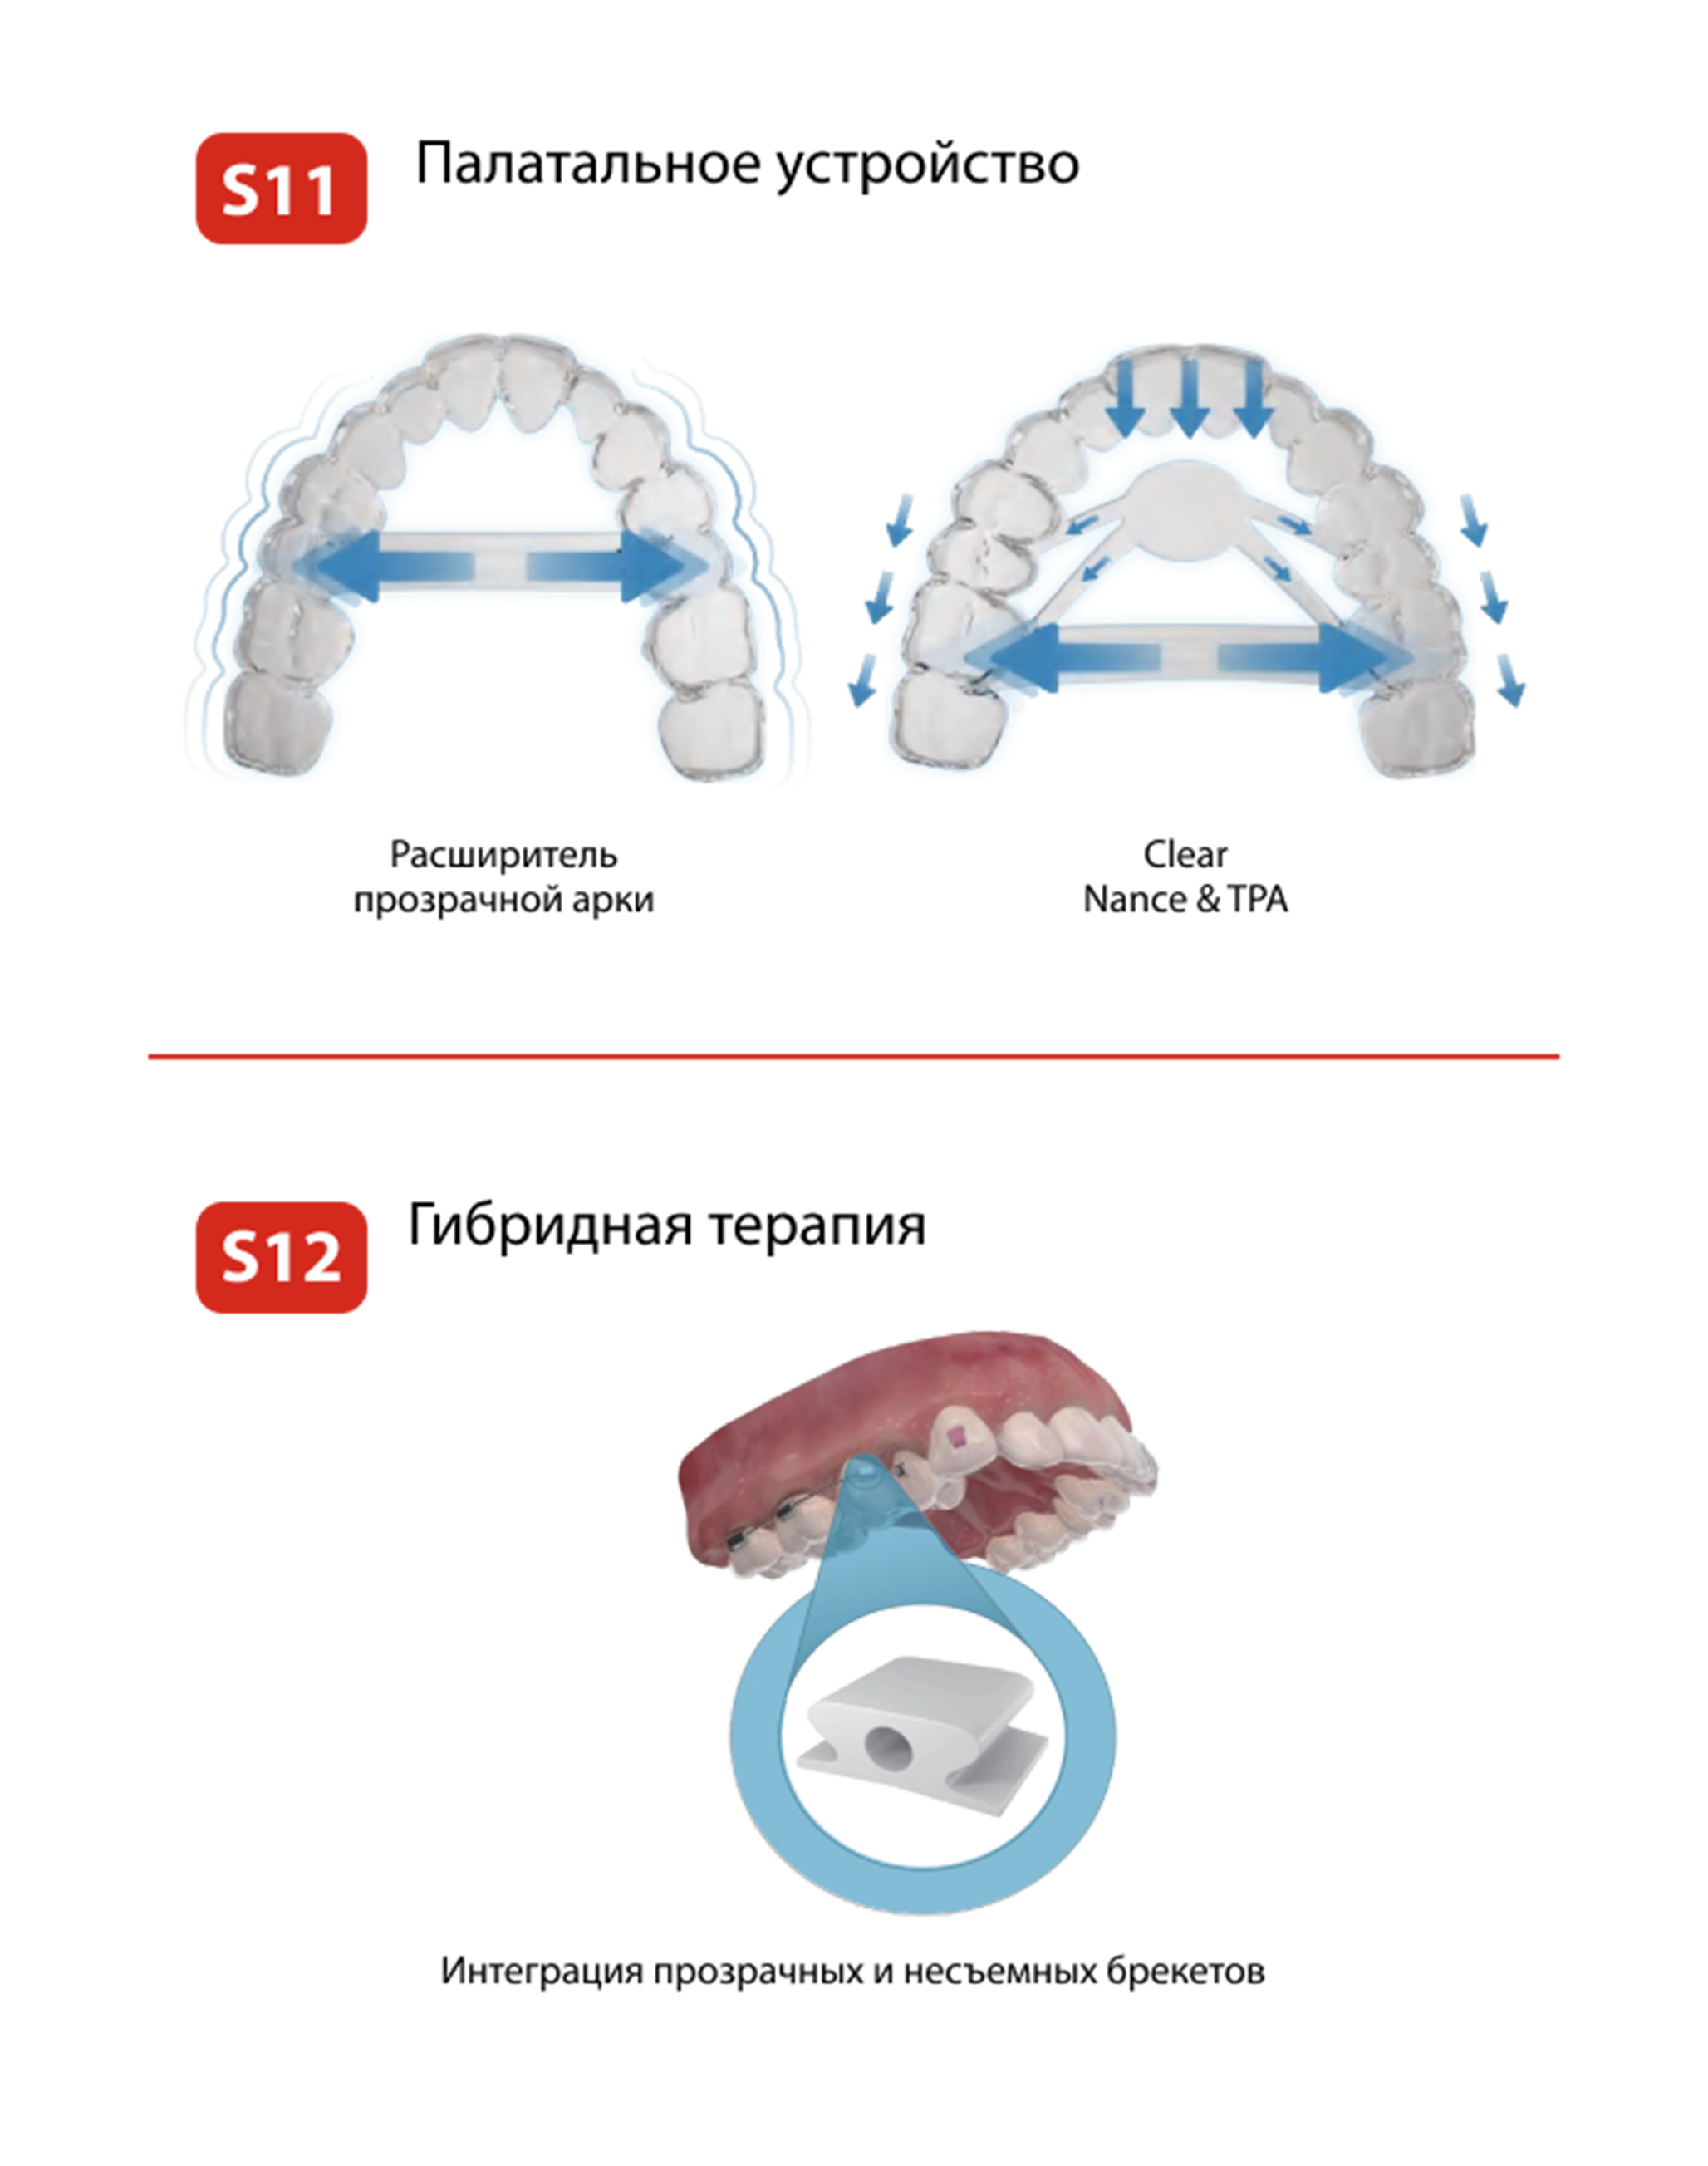

Программное обеспечение

Smartee технологии

Smartee технологии

SMARTEE ТЕХНОЛОГИИ

Продуктовая линейка

ПРОДУКТОВАЯ ЛИНЕЙКА